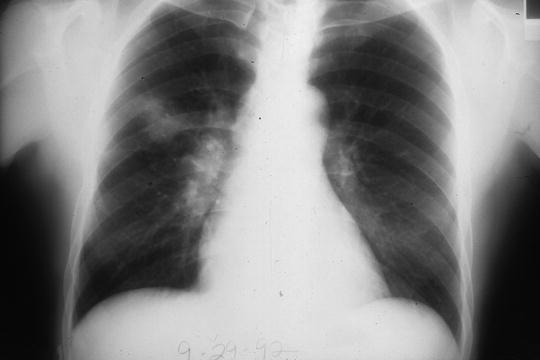

Acute pulmonary aspergillosis in immunosuppressed patients presents with fever, pleuritic chest pain, and dyspnea and has a rapidly progressive downhill course if not treated promptly (see Table 1). Chronic necrotizing pulmonary aspergillosis, occurring mostly in middle-aged to elderly men with chronic obstructive pulmonary disease, is a subacute illness. Low-dose corticosteroids and broad-spectrum antibiotics are predisposing factors for this form of aspergillosis. Patients have fever, cough, purulent sputum, weight loss, and pleuritic chest pain. Multilobar involvement is common, cavity formation is the rule, and extension to the pleura is frequent (see Fig. 3). Progressive pneumonia is the rule unless the diagnosis is made and appropriate therapy given.

Fig. 3.

Chronic necrotizing pulmonary aspergillosis in a middle-aged man with no known risk factors other than chronic obstructive pulmonary disease